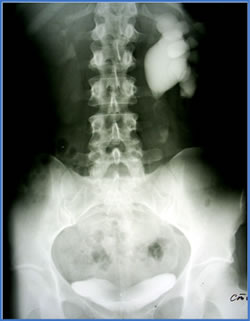

|

Экскреторная

урография |

урография (ноябрь 2002г.) |

Экскреторная урография

(декабрь 2004г.)